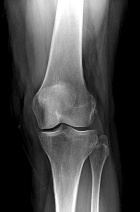

57 year old female presents with c/o L anterior knee pain x5 months. No hx of trauma.

Zoom image: Radiological image Radiological image.